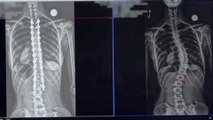

27-YEAR-OLD Steffni was born with a condition that usually only affects males - in fact, her case is so rare that she is thought to be "one in 50 million." Duchenne muscular dystrophy (DMD) is a progressive condition that causes the muscles throughout the body to become weaker over time. When Steffni was diagnosed at three years old, her mom Sally was told that her daughter would not make it past seven years old and despite defying those expectations, her muscles were soon unable to support her spine and she developed severe scoliosis - her spine "curved into a 'S'" shape. This in turn put pressure on her right lung, so doctors suggested operating to glue 15 screws to her skull, connected to a circular band of metal around her head - known as a 'Halo'. The Halo could then be connected to cables above Steffni's head and pulled tight, to stretch out her spine and slow the progression of the scoliosis. Steffni was hoping to have surgery to correct the curve of her spine, but when this was deemed too risky for her, the Halo became permanent - Steffni will live with it for the rest of her life. While she struggled growing up with frequent stares and judgement due to the way the Halo looked, Steffni gradually learned to accept her situation with the support of her mom and brothers Trey and Tyrone. Now, Tyrone sees his sister "living to her best and doing what she likes to do" - with Trey putting this down to his sister being "the strongest person I know." And in typical Steffni fashion, she has found silver linings - like being able to take steps in her special "walker", something she never expected to be able to do as an adult. Now, Steffni's mission is to use her platform as a content creator to reach other young people with disabilities to remind them that if they are having a bad day, "it's just a bad day - not a bad life".<br /><br />Follow Steffni:<br />https://www.tiktok.com/@steffswrld2.0<br />https://www.instagram.com/steffswrld_